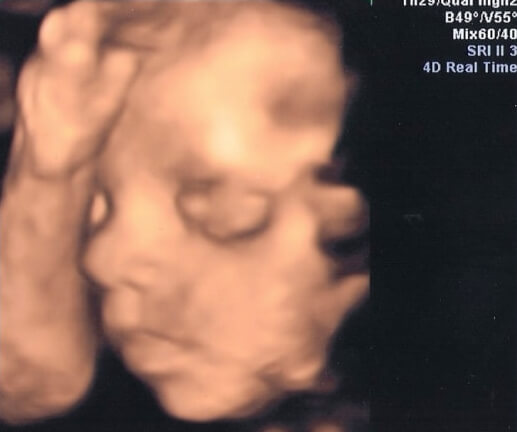

28 Haftalık Bebeğin Ultrason Görüntüsü

Bebeğinizin ultrason görüntüsünün, internetteki fotoğraflardan ya da arkadaşlarınızın ultrason görüntülerinden farklı olması sizi endişelendirmemelidir; çünkü bebeğinizin çok hareketli olduğu bu dönemlerde, anne karnındaki hareketleri ve duruşu, her zaman tahmin edilebilir değildir.

• Bu ayda da bebeğinizin anne karnında göbek kordonunu tuttuğunu ya da parmaklarını emdiğini gözlemleyebilirsiniz.

• Bazı ultrason görüntülerinde bebeğinizin boynuna kordon dolanmış olduğunu görebilir ve telaşlanabilirsiniz. Ancak endişelenecek hiçbir şey yok. Yaygın bilinenin aksine, bebeğinizin bu kadar hareketli olduğu bir dönemde, göbek kordonunu boynuna dolaması, hatta bunu birkaç kez yapması gayet normaldir ve doğumda sorun yaşayacağınız anlamına gelmez.

• 28 haftalık bebeğinizin ultrason görüntülerinde, artık baş aşağı dönmeye başladığını da görebilirsiniz.

• Daha önceki aylarda, bebeğinizde gözlemlediğiniz cılızlık hal, deri altı yağ depolarının dolmasıyla birlikte bu hafta azalabilir ve bebeğinizin giderek tombullaştığını gözlemleyebilirsiniz.